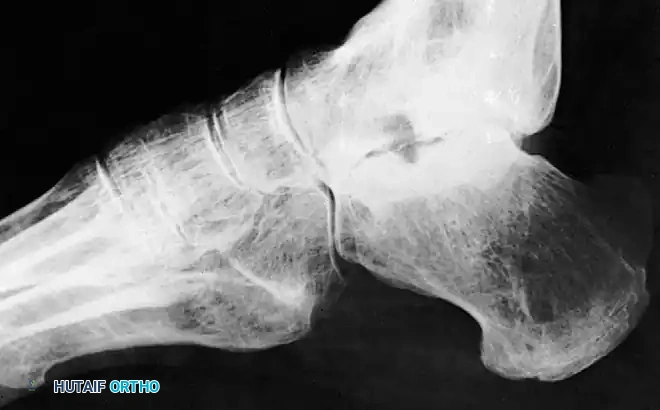

Talar head/neck X-ray example

A high index of suspicion must be maintained for any patient presenting with post-traumatic tenderness in the anterior ankle or midfoot region, as these fractures are notoriously difficult to identify on standard radiographs. While plain films may suggest the injury, a fine-cut Computed Tomography (CT) scan is mandatory for definitive diagnosis, evaluation of articular comminution, and surgical planning.